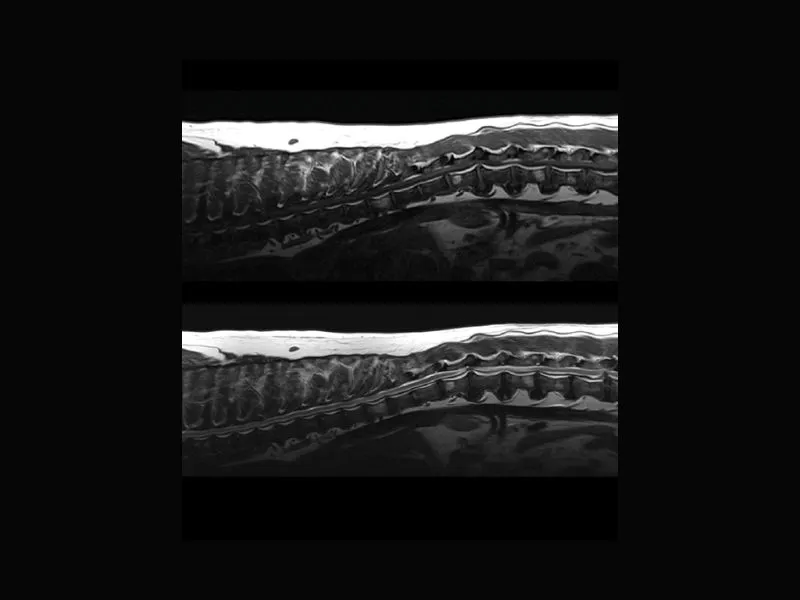

Supreme vet-mr – Multiple protruding discs in thoracolumbar, T1W and T2W slices